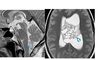

High T2/FLAIR on the dorsal medial thalamus, caudate lobe and putamina bilaterally with diffusion restriction?

A

CJD

Nb - called ‘ hockey stick’ sign

Also look for cortical gyriform restriction

WW3

C = caudate nuclei